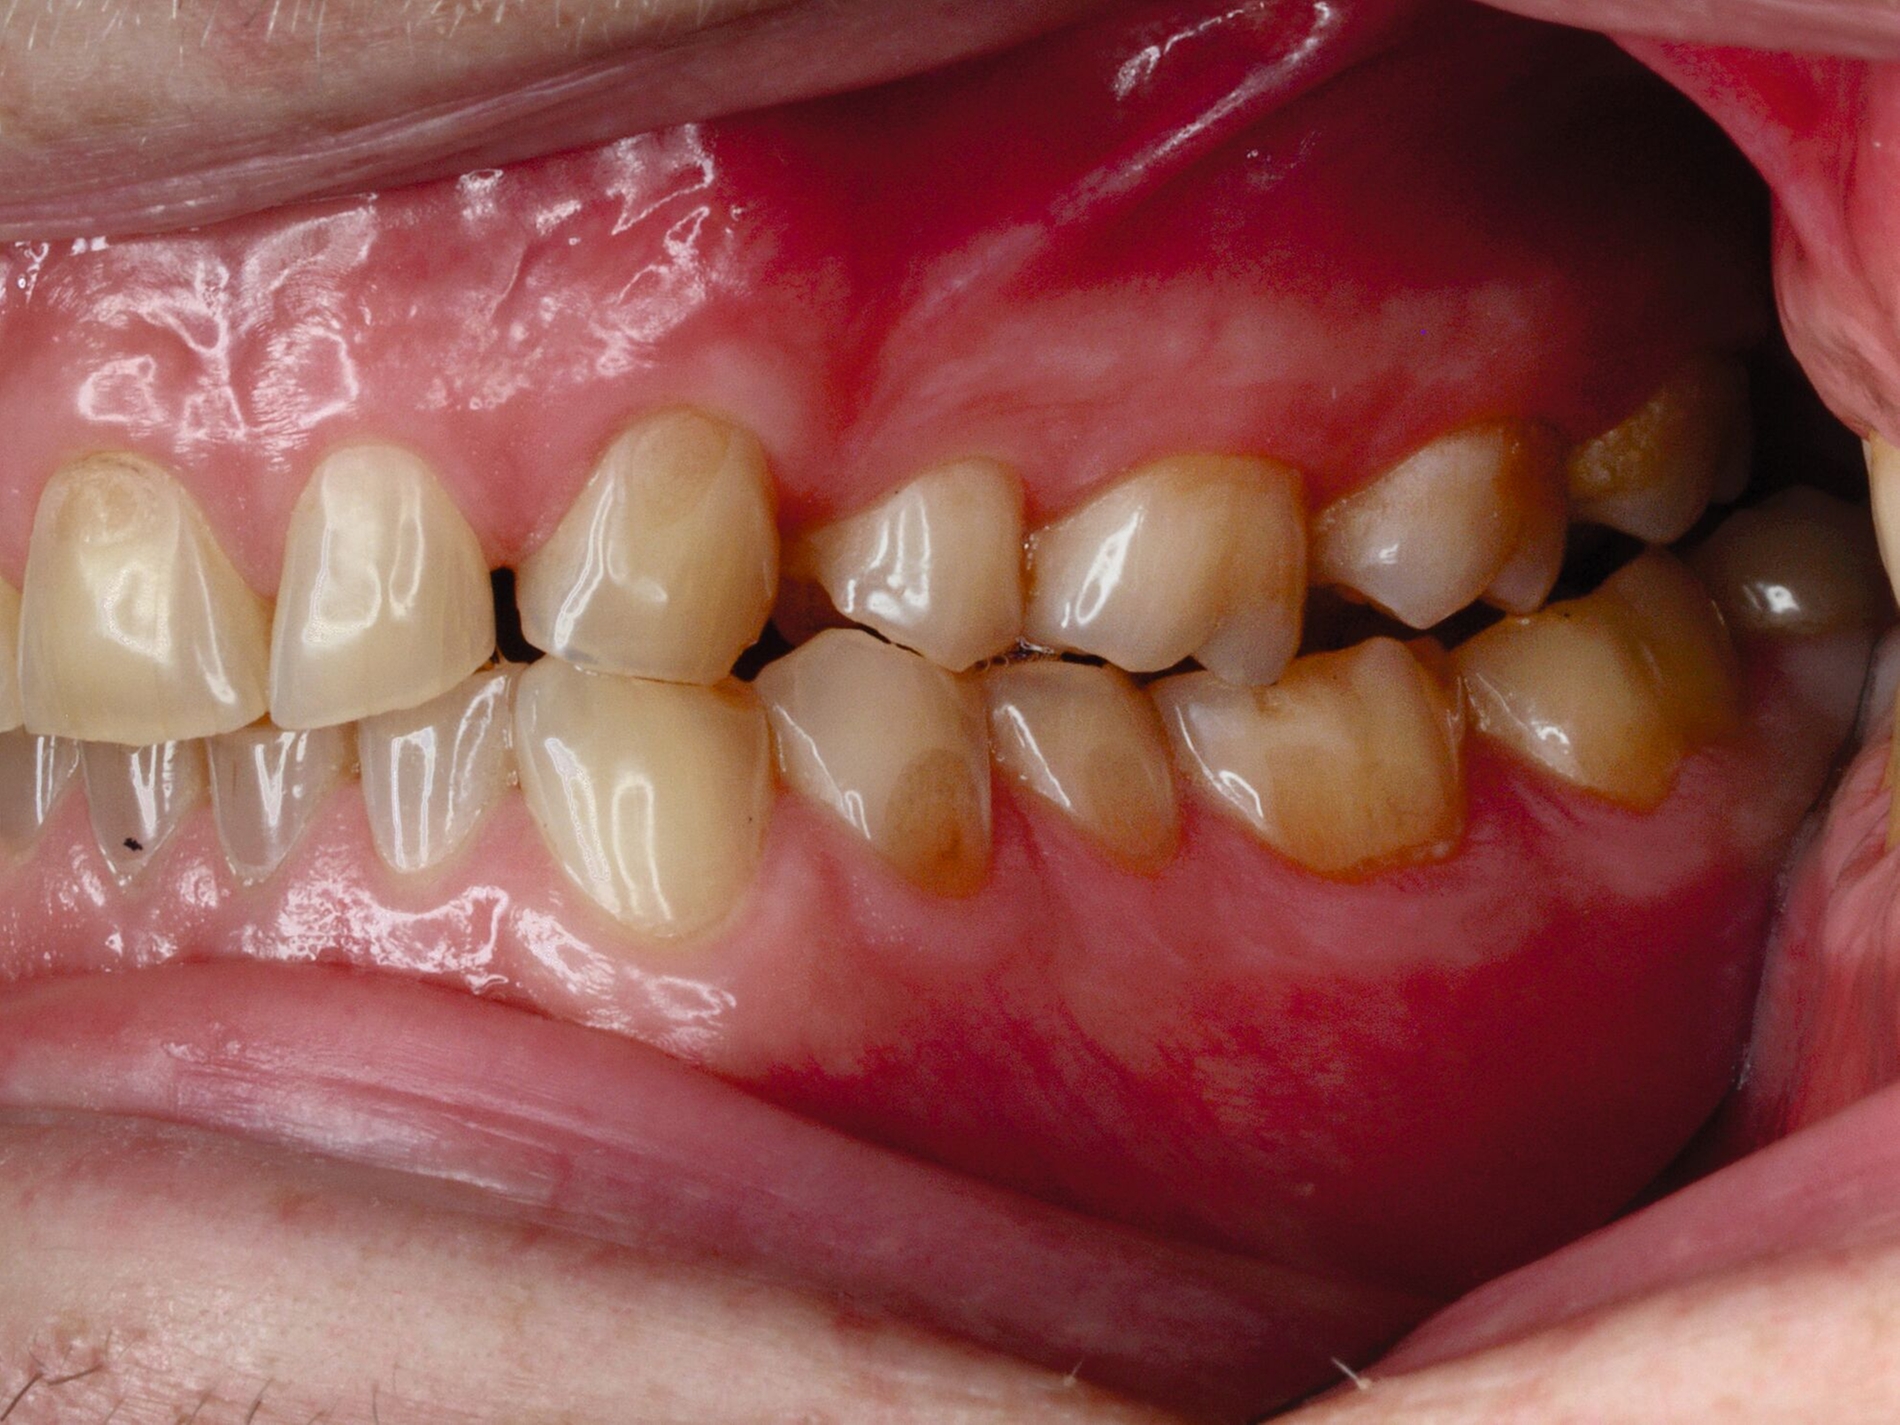

Das unter Beteiligung des Autors entwickelte Tooth Wear Evaluation System (TWES) 2.0 [Wetselaar et al., 2020] identifiziert per Screening Patienten mit erhöhten Verschleißwerten, vergleichbar mit dem PSI in der Parodontologie oder dem CMD-Kurzbefund. Bei auffälligen Werten folgt ein differenzierter Zahnverschleiß-Status einschließlich der Erfassung oraler und vestibulärer Substanzverluste [Wetselaar et al., 2016 sowie von Pathologie-Symptomen und einer strukturierten Diagnose [Tonetti und Sanz, 2019; Wetselaar, 2020]. Den Einsatz in der Praxis illustriert der in den Abbildungen beschriebene Patientenfall aus dem CMD-Centrum Hamburg-Eppendorf.

Zahnverschleiß-Status

Im Unterschied zum Zahnverschleiß-Screening wertet der Zahnverschleiß-Status den höchsten Verschleißgrad pro Zahn aus, und zwar okklusal/inzisal, oral und vestibulär (Abbildungen 4b und 4c, Tabelle 1). Wichtig für die Planung therapeutischer Maßnahmen ist die Frage, welche Zähne okklusal in Kontakt stehen, denn die Behandlung von Zähnen mit erheblichem Zahnverschleiß lässt keinen weiteren Substanzverlust zu und erfordert bei Zähnen in Kontakt absehbar eine Erhöhung der vertikalen Dimension der Okklusion.

Der Zahnverschleiß-Status erfasst auch zehn Kriterien, die nach der Literatur Anzeichen eines pathologischen Geschehens sind. Als pathologisch wird Zahnverschleiß demnach eingeordnet, wenn bei Grad 3 zusätzlich mindestens ein Pathologie-Kriterium vorliegt (Abbildung 6).

Ergänzt wird der Zahnverschleiß-Status durch 20 Merkmale, die jeweils chemischen und mechanischen Ursachen zugeordnet sind und in der summativen Auswertung zeigen, welche Ursachen offensichtlich dem Geschehen zugrunde liegen. Dies ist auch bei vermeintlich eindeutigen Fällen hilfreich, da zuweilen mehrere Faktoren ineinandergreifen, die dann möglichst alle abzustellen sind, bei erheblichem oder extremem pathologischem Zahnverschleiß einhergehend mit einer eventuellen restaurativen Therapie.

Wichtig für das Therapiekonzept ist zudem der Umfang des Zahnverschleißes. Die Auswertung unterscheidet daher lokalisierten und generalisierten Zahnverschleiß.

Im Beispiel ist daher die Diagnose ein generalisierter erheblicher und lokalisierter moderater pathologischer Zahnverschleiß überwiegend mechanischer und zudem chemischer Ursache. Die sich daraus ableitende Erkenntnis ist, dass in allen Sextanten Zähne freiliegende Dentinkerne aufweisen (generalisierter moderater Zahnverschleiß), dass darüber hinaus Zähne erheblich geschädigt und somit gefährdet sind, dass Merkmale eines pathologischen Geschehens bestehen – und dass als Ursache neben dem dominierenden Bruxismus ein Säureeinfluss hinzukommt.

Auch wenn Restaurationen nach Möglichkeit vermieden werden sollten, ist deren Verfügbarkeit für die Betroffenen individuell höchst wichtig, weil sie bestehende Schmerzen beseitigt, die verlorengegangene Kauleistung wiederherstellt und ästhetische und nicht zuletzt auch phonetische Einschränkungen aufhebt. Bei dem in den Abbildungen beschriebenen Fall korrelierte der erhebliche Zahnverschleiß mit der Lokalisation der Zahnschmerzen des Patienten. Direkte Restaurationen mit Kompositen hatten keinen Bestand. Die durchgeführte restaurative Behandlung hingegen hat Bestand, die Schmerzen waren danach umgehend verschwunden und sind seit zehn Jahren nicht wiedergekehrt.